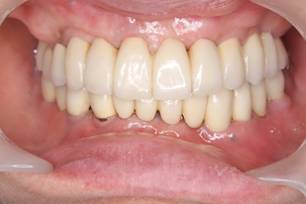

術後。上部構造はハイブリッドレジンです。しっかり嚙めるようになり喜んでいただきました。

上部構造装着後6年。ハイブリッドレジンを使用したため、少し艶がなくなってきました。上部構造の材料には金属、ハイブリッドレジン、セラミックなどがあります。セラミックはきれいですが欠けやすいため、最近はフルジルコニアを使っています。